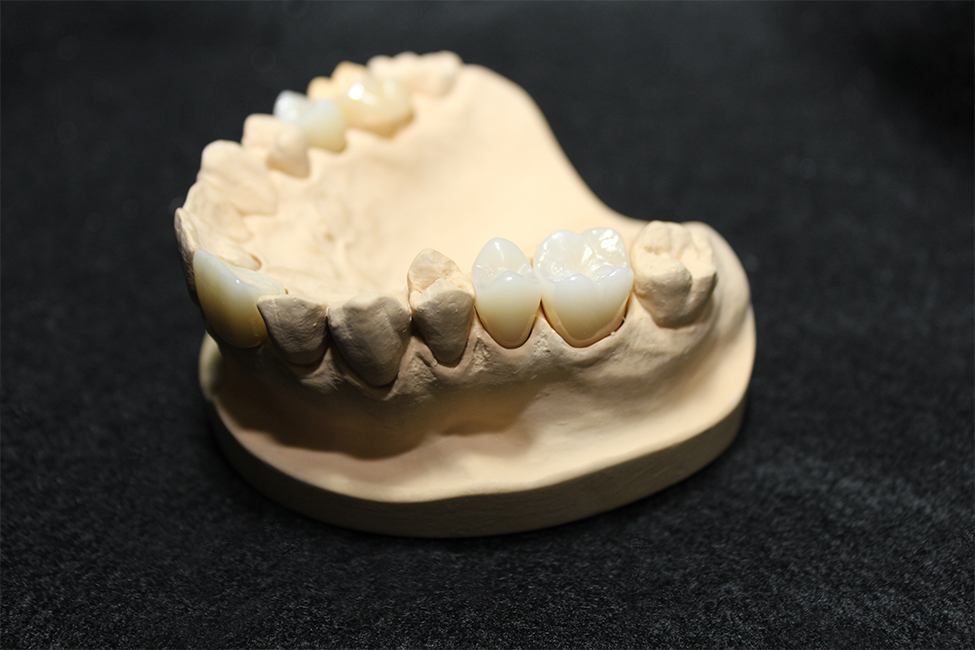

CAD/CAM冠

5軸の加工機で精密に加工します。

当ラボではクラウン、インレーともに使用するブロックはYAMAKINのCADCAMブロックを採用しております。

安定した強度があり、前歯から大臼歯にかけての自然な色調の調和が取れています。